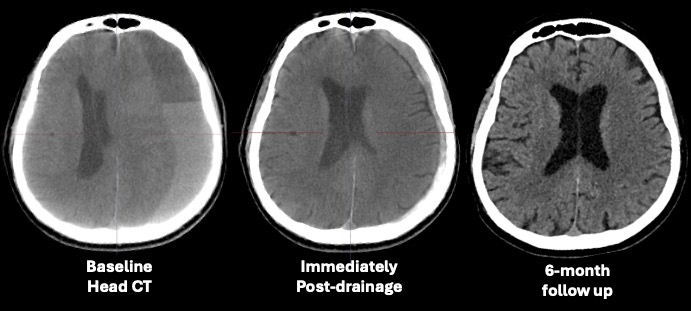

Abstract Body: Introduction: surgical evacuation of non-acute subdural hematoma (SDH) for rapid brain decompression and middle meningeal artery embolization (MMAe) to prevent re-bleeding as a surgical adjunct is becoming a dominant treatment paradigm of symptomatic SDH. However, this approach requires two different interventions with their associated risks, prolonged ICU/hospital stay and increased costs. An endovascular technology was developed for transvascular access to the intradural space, drainage of SDH and MMAe. We report the procedural results and 6-month follow up of the first three consecutive patients treated with this technology. Methods: a prospective, single-arm, first-in-human study (EMBODRAIN Study) was conducted to evaluate the safety and feasibility of endovascular drainage of non-acute SDH and MMAe using a purpose-built endovascular technology (Endovascular Horizons, Inc). Results: three consecutive patients (males, 76 years ±5) were treated and completed the pre-specified 6 months follow-up. Acute clinical success (defined as MMAe and transvascular drainage of the SDH with no conversion to open surgical drainage) and acute technical success (defined as ability to create a leak-proof transvascular passageway and access the intradural space, drain the SDH and occlude the MMA) was achieved in all cases (3/3). No Serious Adverse Events (SAE) were recorded at 30-days. The SDH volume at baseline (before intervention) was on average 296 ml, and decreased immediately post-procedurally to 25ml, corresponding to a 92% volumetric reduction on average. The SDH thickness at baseline was on average 25 mm, and decreased post-procedurally to 11 mm. The midline shift at baseline was on average 8 mm, and decreased post-procedurally to 3 mm. At 6-months the head CTs showed an average SDH volume of 8ml, SDH thickness of 3mm, and midline shift of 0mm. The pre-morbid Modified Rankin Scale Score was 0.33 on average, was 3.66 at presentation with the SDH, and decreased to an average of 2.33 at 72hrs post-intervention. At 6 weeks, 3 months and 6 months follow-up, all patients were found to have a mRS of 0. During the study duration there were no SDH recurrence or progression requiring surgery, hospital readmission and deterioration in neurological function. Conclusions: this report presents the first cohort of patients with symptomatic non-acute subdural hematomas to successfully undergo endovascular drainage of SDH and MMAe in a single, fully endovascular procedure.